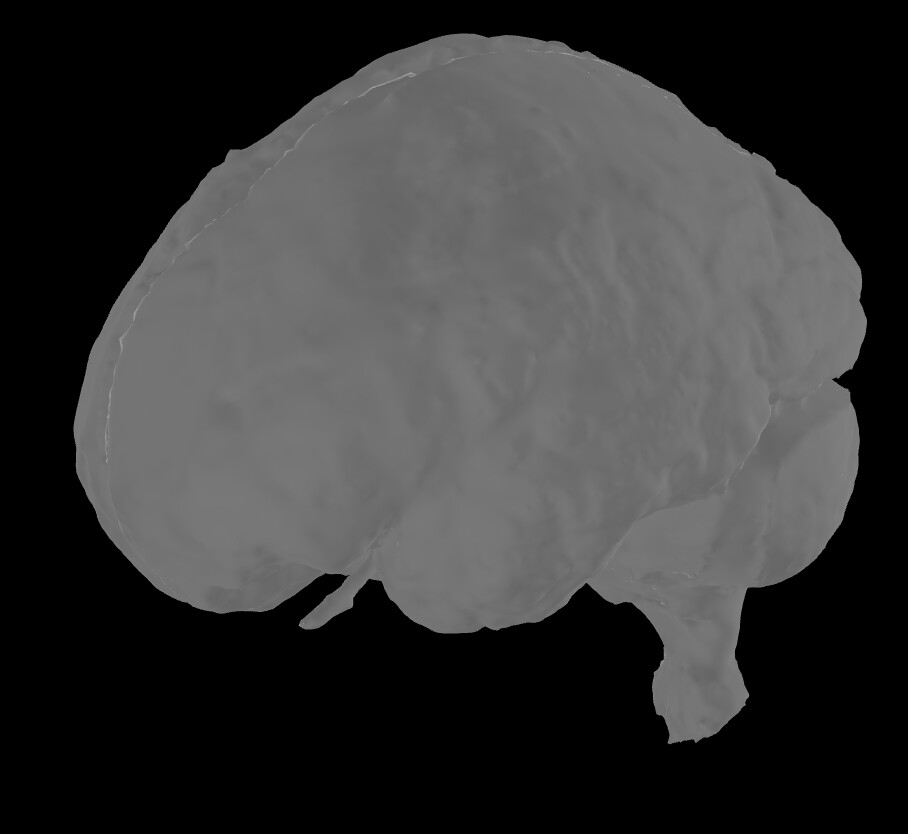

As a matter of fact, while the FEM model seems to do a good tissue characterisation, all the surfaces I have extracted within Brainstorm are wrong. For example, the scalp seems to have some skull embedded within

or, for example, the skull seems the CSF(?)